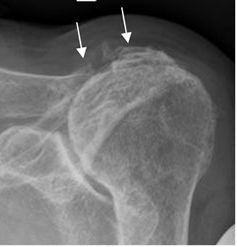

Osteopenia con erosiones óseas, formación de pannus y deformidad. El compromiso es simétrico. En los casos avanzados, la disminución del espacio articular es uniforme. Es clásica la reabsorción del tercio distal de la clavícula. (Fig 162).

Fig 162. Artritis reumatoidea.

Rx AP de hombro. Osteopenia generalizada. Reabsorción del acromión y el tercio distal de la clavícula, hallazgos típicos de AR.